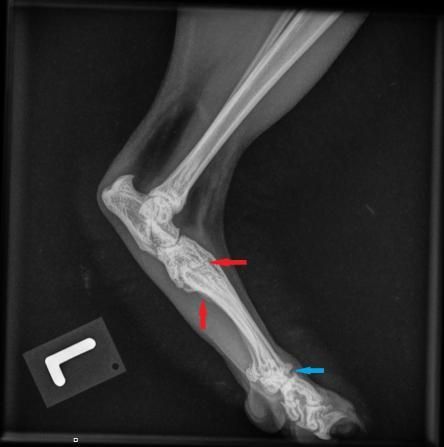

Die Besitzerin berichtet, dass der Kater recht lahmheitsfrei laufe, aber nicht über eine grosse Sprungkraft verfüge. Die Beine von Maxwell sind eher kurz und er scheint hinten und vorne X-beinig. Der Gang der Katze wirkt staksig; eine eigentliche Lahmheit ist nicht zu sehen. Um Aufschluss über die Situation in den Gelenken zu erhalten, werden die Vorderpfoten/Handgelenke, Hinterpfoten/Fusswurzelgelenke und die Wirbelsäule geröntgt. Es ist zu erkennen, dass Hand- und Fusswurzelgelenke gegenüber der Normalsituation eine X-beinigkeit (Valgisierung) aufweisen, an verschiedenen Stellen Anzeichen einer Arthrose vorhanden sind und insbesondere die Mittelhand- und Mittelfussknochen kurz und gedrungen erscheinen. Ein Teil der Fusswurzelknochen von Maxwell sind ausserdem zu einem einzigen Knochen verwachsen.

Sprunggelenk links Maxwell Sprunggelenk links normale Katze